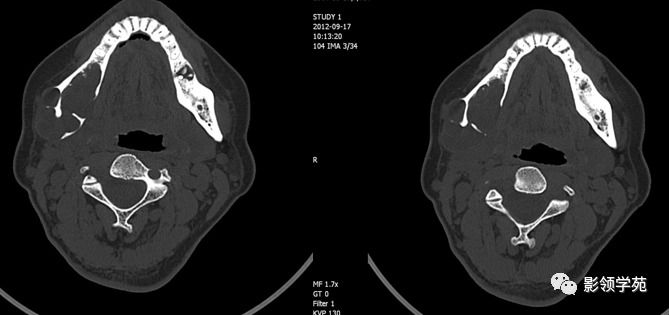

医学影像颌骨放射性骨坏死的ct表现

病变ct片(2)